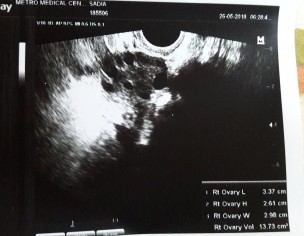

Asking for Self, Female, 28 years old, UAE

Hello I want to coneive for 7 years Yesterday i go to doc they said my utrus size is little small Can u u check the scan report and tell me can i conceive with this size Really worried plz help